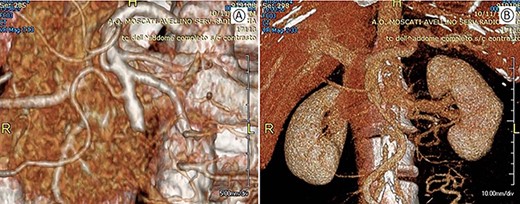

This case involved a 63-year-old man who had a history of hypertension, psoriasis and atherosclerosis. He referred the appearance of a light epigastric pain and general discomfort. Laboratory tests were normal. Abdominal ultrasonography was negative as well as the esophagogastroduodenoscopy and colonoscopy. Abdominal computer tomography (CT-scan) with contrast showed a solid mass of about 42 × 31 mm in the mesenteric adipose tissue, incorporating the distal part of the SMA and the superior mesenteric vein (SMV) (Fig. 1). A fluorodeoxyglucose positron imaging tomography/computed tomography (CT) showed an increased uptake (SUV 5.2) at the level of the mesenteric mass.

Preoperative CT; (A) arterial phase: the arrow shows the neoplastic mass traversed by the superior mesenteric artery. (B) Venous phase: the arrow shows the neoplastic mass in contact with the superior mesenteric vein.